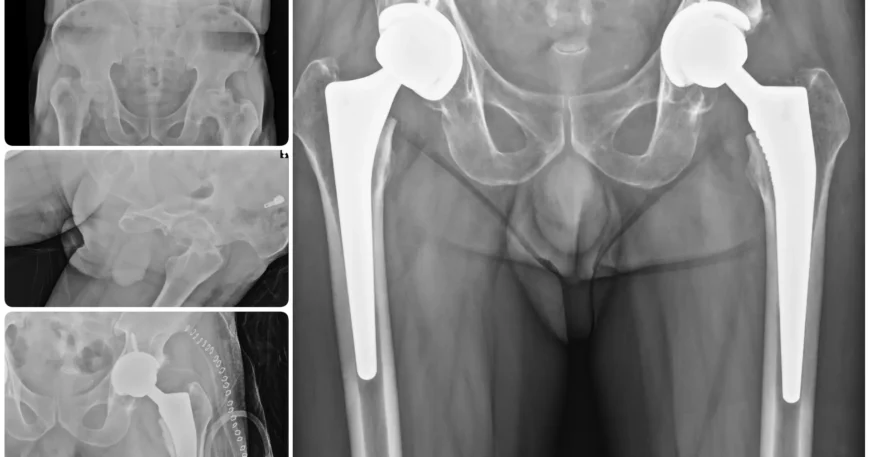

Bilateral AVN Hip Successfully Treated with Total Hip Replacement

At Balanku Hospital, we specialize in advanced orthopedic treatments that restore mobility and improve quality of life. We are pleased to share the successful recovery of Mr. Sheikh Sameer, who was treated for bilateral avascular necrosis (AVN) of the hip joints.

After detailed clinical evaluation and imaging studies, the orthopedic team at Balanku Hospital recommended Bilateral Total Hip Replacement (THR) as the most effective solution to relieve pain and restore function.

The patient successfully underwent Bilateral Total Hip Replacement surgery, performed with precision using advanced joint replacement techniques. Our orthopedic department is also experienced in complex reconstruction methods, including Ilizarov techniques, ensuring comprehensive care for a wide range of orthopedic conditions.